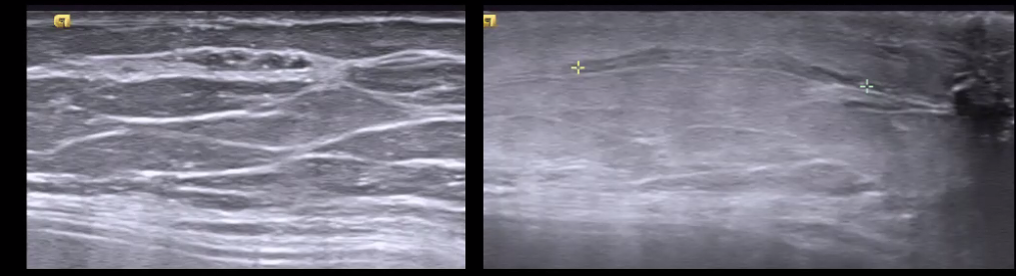

DCIS on US. ectactic ducts filled with debris and calcifications